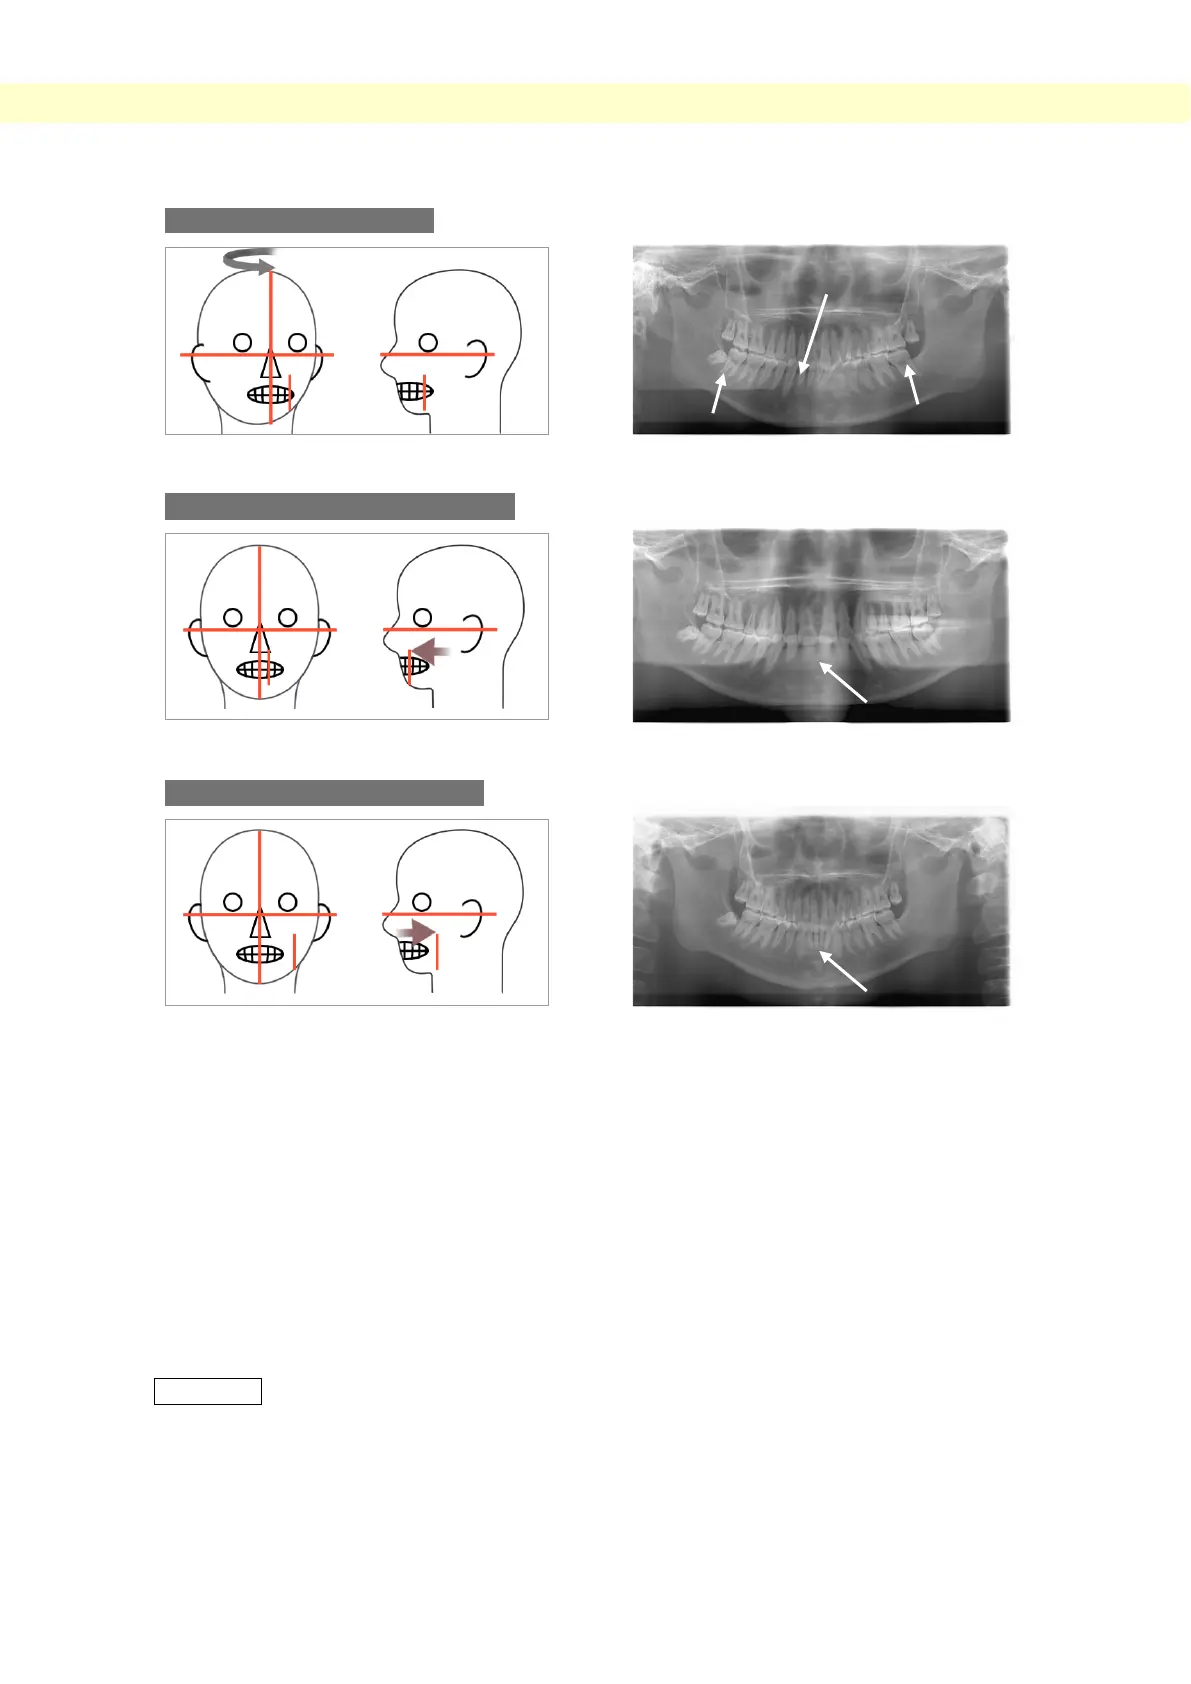

Patient Looking to the left

Image-layer Beam too far forward

Image-layer Beam too far back